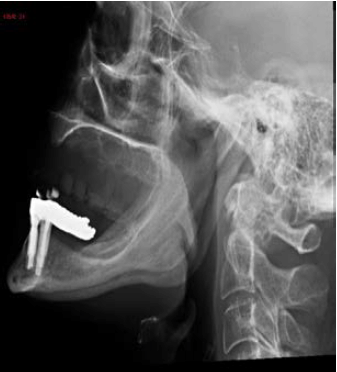

Uma paciente de 60 anos realizou radiografia de seios da face com queixa de cefaleia. Frente às imagens, considera-se que há:

A

sinusopatia aguda, com níveis hidroaéreos nos seios maxilares e velamento de células etmoidais, e doença hipofisária com aumento de volume selar.

B

sinusopatia crônica, com espessamento mucoso nos seios maxilares e células etmoidais, e lesão expansiva da parede posterior do cavum.

C

pólipos nos seios maxilares e células etmoidais, e aumento do espaço articular atlanto-odontoide, provavelmente por artrite reumatoide.

D

espessamento mucoso dos seios maxilares e lesão insuflante do palato, provavelmente por hiperparatiroidismo secundário.

E

sinusopatia aguda, com níveis hidroaéreos nos seios maxilares, e esclerose da asa do esfenoide, podendo corresponder à meningeoma à direita.